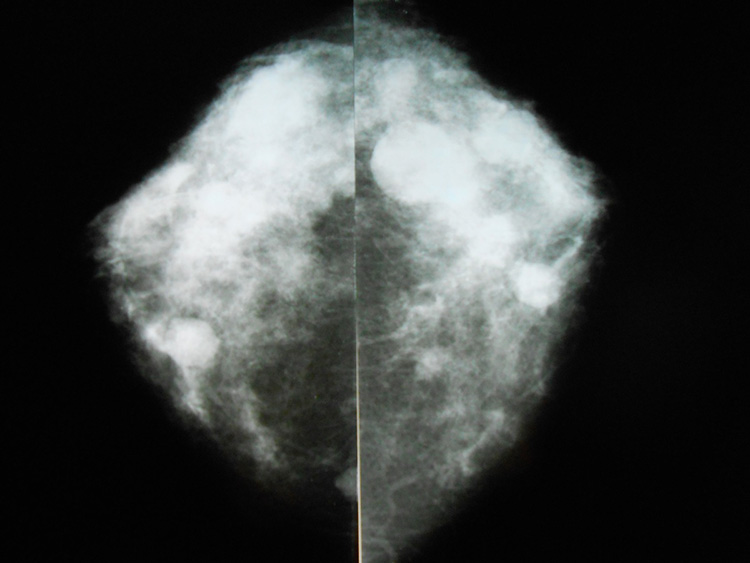

УЗИ молочных желез — информативный и безопасный метод диагностики, с помощью которого можно точно оценить состояние желез, обнаружить доброкачественные и злокачественные образования, уточнить диагноз. Это доступное по цене исследование безвредно и не несет лучевой нагрузки. Оно имеет большое значение в ранней диагностике заболеваний и нередко применяется в профилактических целях. На УЗИ может направить маммолог, онколог, эндокринолог, гинеколог.

Сделать УЗИ молочных желез можно в качестве первичной диагностики и для уточнения уже предполагаемого диагноза. Метод основывается на способности высокочастотных ультразвуковых волн с различной скоростью отражаться от тканей с разной плотностью.

С помощью ультразвуковой диагностики можно обнаружить следующие заболевания:

- воспалительные заболевания — мастит, абсцессы, лактостаз у кормящих женщин, мастопатии различного происхождения и типа — фиброзно-кистозные, диффузные и пр.;

- врожденные аномалии молочной железы;

- рак;

- кисты и доброкачественные опухоли;

кальцинаты.

Для оценки кровотока в тканях молочных желез используется доплерография. Данные, полученные в результате биопсии под контролем УЗ-аппарата, могут сказать о природе и характере образований в молочных железах.

Кому противопоказано

УЗИ практически не имеет противопоказаний. Однако важно отметить, что информативность обследования груди таким способом у женщин молодого возраста выше, поскольку ткани молочных желез с возрастом становятся более рыхлыми. Поэтому после 40 лет УЗИ в большинстве случаев сочетается с рентген-диагностикой (маммографией).